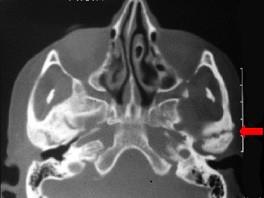

患儿,5岁,外伤后逐渐出现张口困难,咬合关系错乱,髁突动度减弱,外观及X 线检查结果如图。最可能的诊断是  (    )